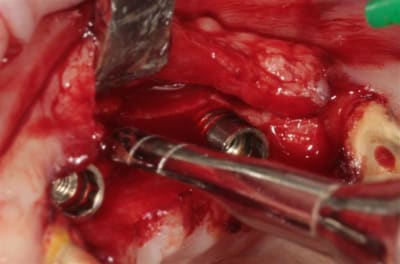

OK nous n'y sommes pas encore, mais je me suis fais une petite intervention sympa ce matin, avec un nouvel outil (qui n'est pas sur les photos ....because chut!) qui devrait permettre de simplifier la pratique de l'expansion, afin que tout un chacun puisse pratiquer ce sport sympa, et si tout va bien je pourrais vous en parler (peut être) en Juin.

crête en lame d'1 mm..pour 23/24/26

Axioms 3.4 x10 (2) et 3.4x 8

Mais, ce post est surtout provoqué car j'ai utilisé un nouvel outil pour l'expansion et si la suite le confirme, les ostéotomes "classiques" pourraient bien êtres renvoyés sur l’étagère des outils du souvenir..